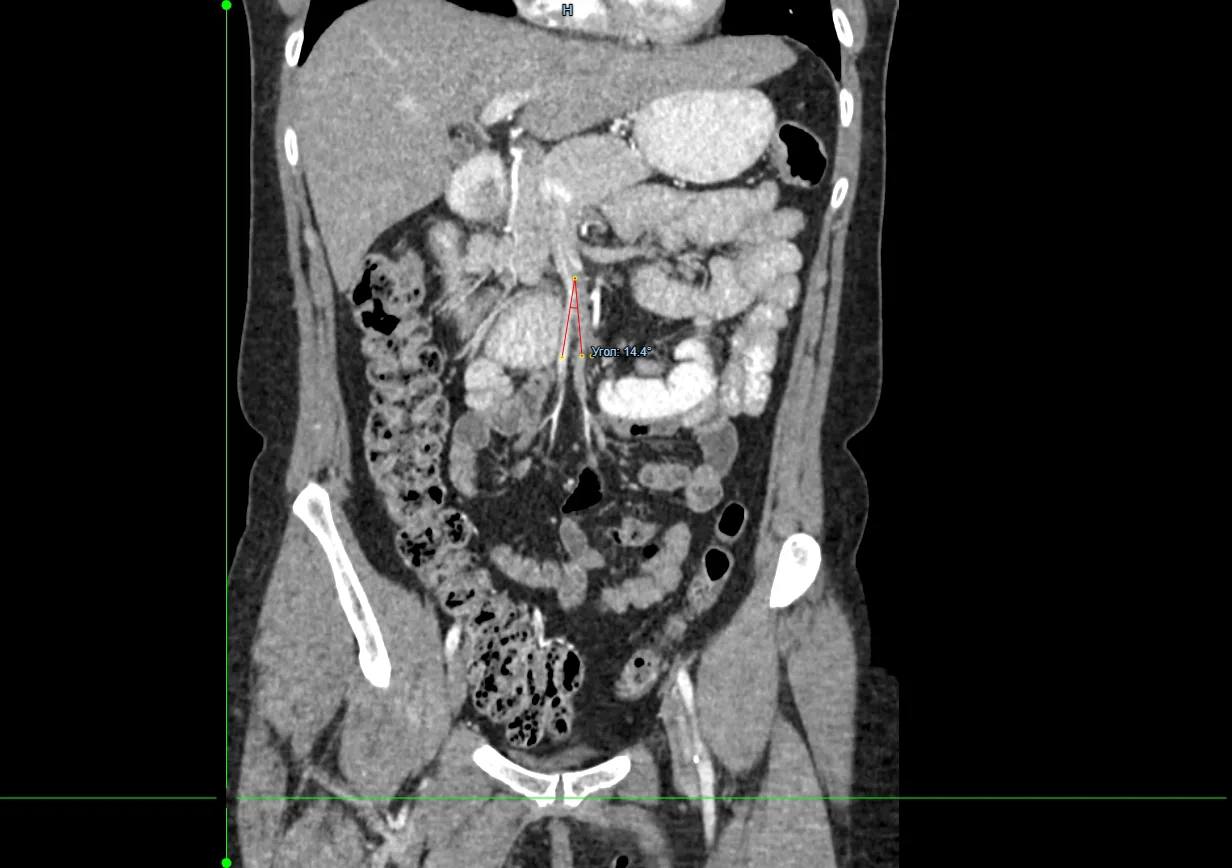

Врачи хирургического отделения №3 Красноярской межрайонной клинической больницы №20 им. И.С. Берзона провели операцию 49-летней пациентке с синдромом Уилки. Из-за него женщина долго не могла нормально питаться и сильно похудела.